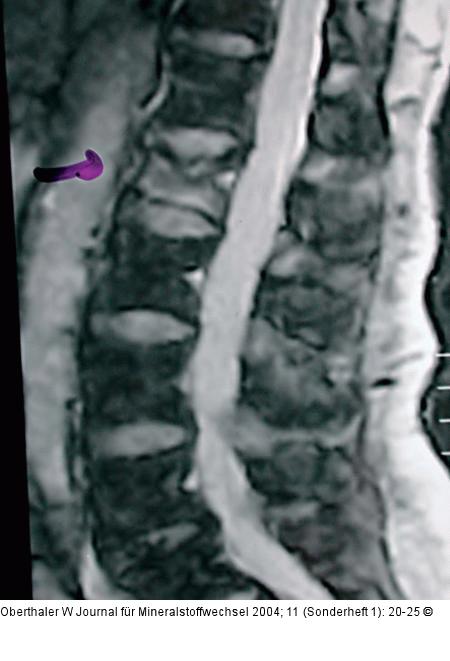

Abbildung 1: Vertebroplastie Erst das MRI zeigt einen eindeutigen Befund: Ödem im Bereich der Läsion |

Erst das MRI zeigt einen eindeutigen Befund: Ödem im Bereich der Läsion |